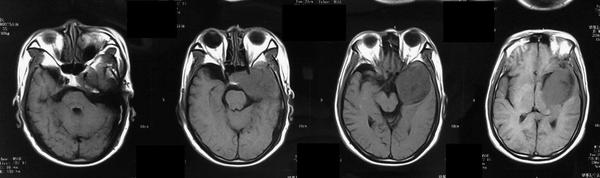

CT表现呈等密度、混杂密度、病灶边缘见小片高密度钙化。所有病灶边缘均光滑,与邻近脑实质分界清晰,无瘤周水肿,增强检查后均呈显著强化,强化均匀、部分不均匀,颈内动脉海绵窦段受压移位,部分病灶包绕血管,颈内动脉未见明显狭窄。CT骨窗上有中颅窝底、前床突及岩尖部等有骨质吸收,未见明显骨质增生。

MRI表现:病灶中相对脑实质来说T WI上呈等信号,或稍低信号,信号均匀,少数内部见小片高信号。T WI及T 一FLAIR上均为明显高信号。CSHAs的血供丰富及解剖结构较复杂,术前误诊率和术后致残率均较高,掌握其CT、MR及DSA等各种影像学检查方面的特征性表现,可提高术前定位及定性诊断的准确率,对于临床治疗方案的制定、确定手术入路以及减少手术致残及致死率有着十分重要的意义。

有学者认为海绵窦海绵状血管瘤与雌激素、孕激素和促性腺激素的水平有关 。而Ohata等则认为这是颅内高血流状态和动脉收缩压升高所致。有文献报道部分患者有腺垂体功能减退的症状,与肿瘤向鞍内生长有关。海绵窦海绵状血管瘤的影像学特点为同时累及鞍旁和鞍内的单发大肿块,呈哑铃状,密度多均匀而少出血和钙化,其在CT扫描时呈等或稍高密度,瘤内常无钙化,可侵蚀颅骨,但一般不伴骨质增生。MRI扫描时T wI明显高信号和显著均质强化是其重要的诊断依据 ” 。